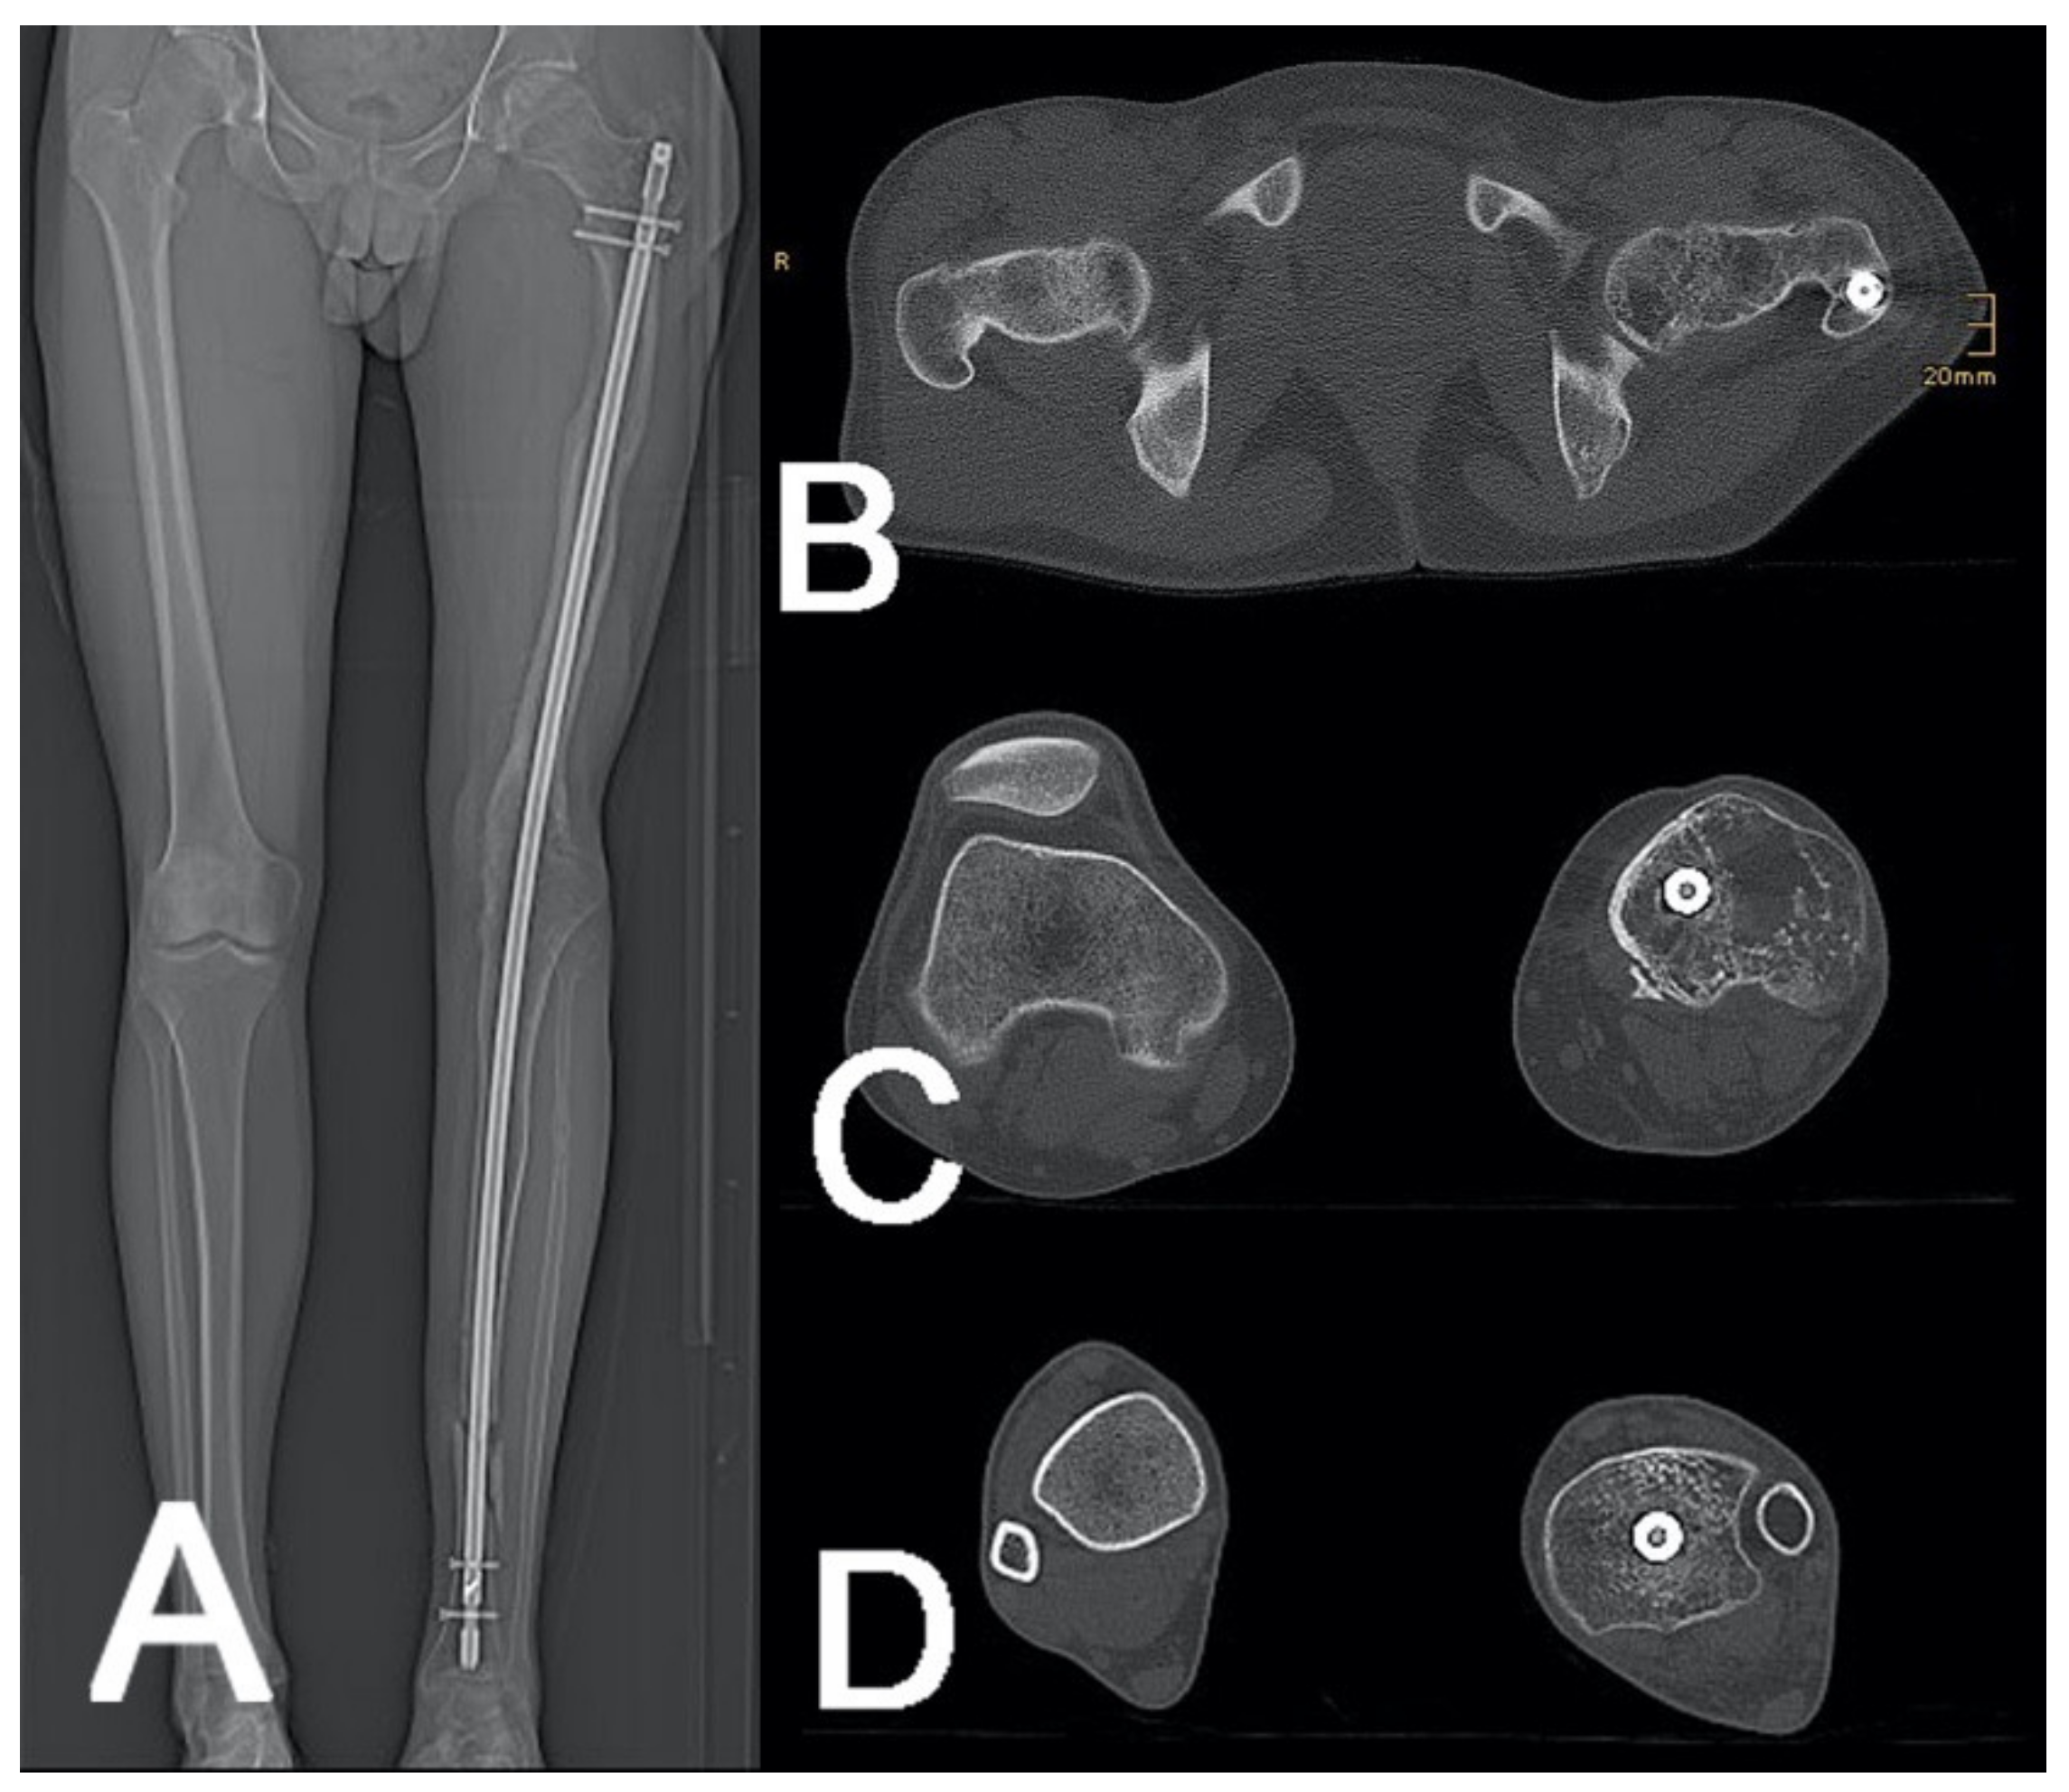

2.4.6. Rotational CT/Torsion CT

| Rotational CT | 2 |